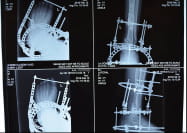

Воїн 93-ї моторизованої бригади Володимир був важко поранений вибухом міни неподалік Донецького аеропорту. Він дивом уникнув повної травматичної ампутації, однак традиційні методики ортопедії і травматології не передбачають лікування таких великих поранень. Тому єдине, що було зроблено бійцю в госпіталях – видалення уламків кістки та лікування запалення. Німецький госпіталь, який брав на лікування Володимира, також не зміг допомогти. Бійцю загрожує інвалідність, але клітинні технології дозволяють відновити втрачену через поранення кістку.

Боєць 30 моторизованої бригади Андрій потрапив під танковий обстріл російських окупантів неподалік Савур-Могили. Зазнав важкої травми ноги (кістку розтрощено), численних осколкових травм тіла та контузії. Героя лікували у госпіталях та лікарнях Харкова, Вінниці та Житомира. Він переніс 6 операцій, але натепер традиційна медицина вже нічого не може йому запропонувати, щоб зберегти ногу, і йому загрожує ампутація. Клітинні технології допоможуть врятувати ногу та максимально повернути нозі її функції.